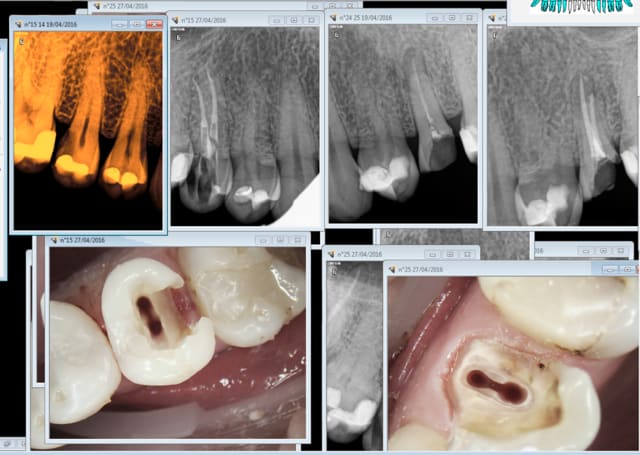

Exemples Si la 25 ca ne fait pas de doute la 15 y a droit aussi car limite sous gingivale et en plus je fais ce que je veux. Et en plus le patient est d'accord car mieux remboursé. Merde. -).

De plus les soucis ne proviennent pas du type de reconstitution qui est de l'enculage de mouches à partir du moment ou tu délabres le peu qui reste en faisant une couronne, mais de la qualité de l'endo sous jacente.

Je l'ai bichonnée en endo au contraire de la 25 qui non seulement a pété car non couronnée mais en plus a subi un tt endo de m.....